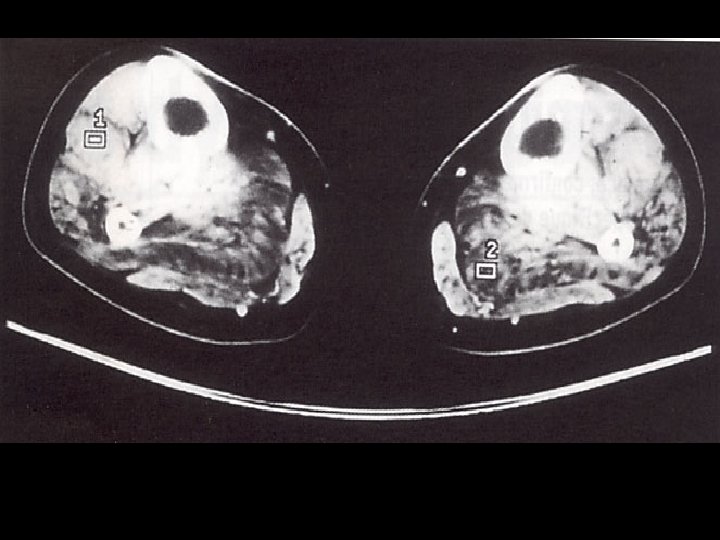

Démarche diagnostic: les examen complementaires Investigation à valeur d’orientation: - Imagerie (scanner, IRM musculaire) Complément indispensable de l’analyse clinique: dépistage atteinte infraclinique, cartographie muscles affectés, préalable à une biopsie IRM si suspicion d’une pathologie inflammatoire; dans les autres cas scanner !!! - Electromyogramme (EMG): Pour évaluer le caractère myogène, recher une myotonie, Stimulation répétitive pour recher une myasthénie etc.